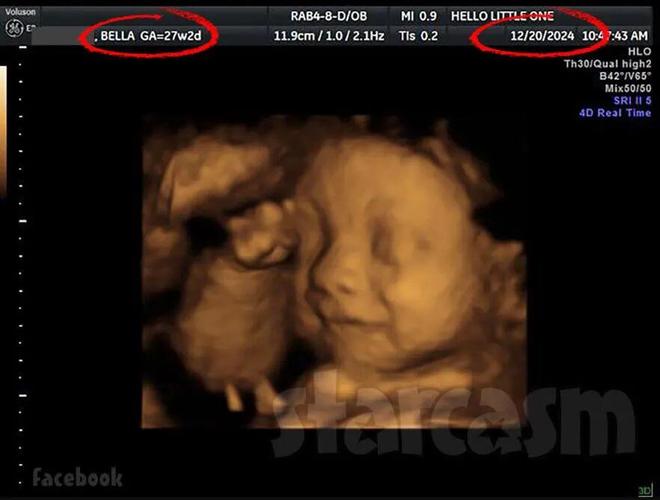

她后来在Facebook上晒过B超单,做B超的时间是2024年12月20日,当时贝拉怀孕已经27周,能推算出她受孕的时间大概在2024年6月。

(贝拉的B超单)